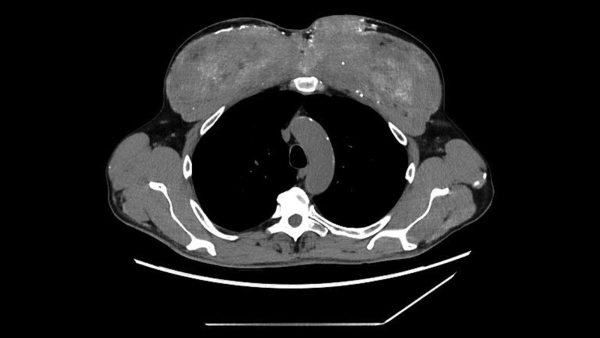

Комп'ютерна томографія грудної клітки чоловіка виявила кальцифіковані ділянки грудних м'язів, куди він раніше вводив олії для покращення м'язової маси. (Зображення надано: Markowska et al. BMC Nephrol 26, 476 (2025). (CC 4.0))

Чоловік загалом був стабільним, але медичний огляд показав помітні зміни в м’язах плеча та грудей, що відповідали порушенням, виявленим на сканах. Потім лікарі переглянули історію хвороби пацієнта, і він поділився важливою деталлю: приблизно 30 років тому він почав отримувати «невідомі внутрішньом’язові ін’єкції (ймовірно, що містять тестостерон)» у м’язи грудей та плечей для їх збільшення, згідно зі звітом про його випадок.

Діагноз: під мікроскопом м'яз був заповнений силіконополімерною речовиною на масляній основі та оточений щільними кальцієвими відкладеннями. Команда вчених дійшла висновку, що попередні ін'єкції чоловіка в м'язи, ймовірно, містили синтол, речовину, що складається переважно з олії, яка візуально «наповнює» м'язи, по суті, надуваючи їх, як водяні кульки.

У цьому випадку синтол викликав стійку реакцію на чужорідне тіло — організм, по суті, реагував на матеріал, який він не міг розщепити. З часом ця реакція призвела до рубцювання та кальцифікації, що призвело до накопичення великої кількості кальцію всередині м'яза. І зрештою цей кальцій потрапив у його кров.